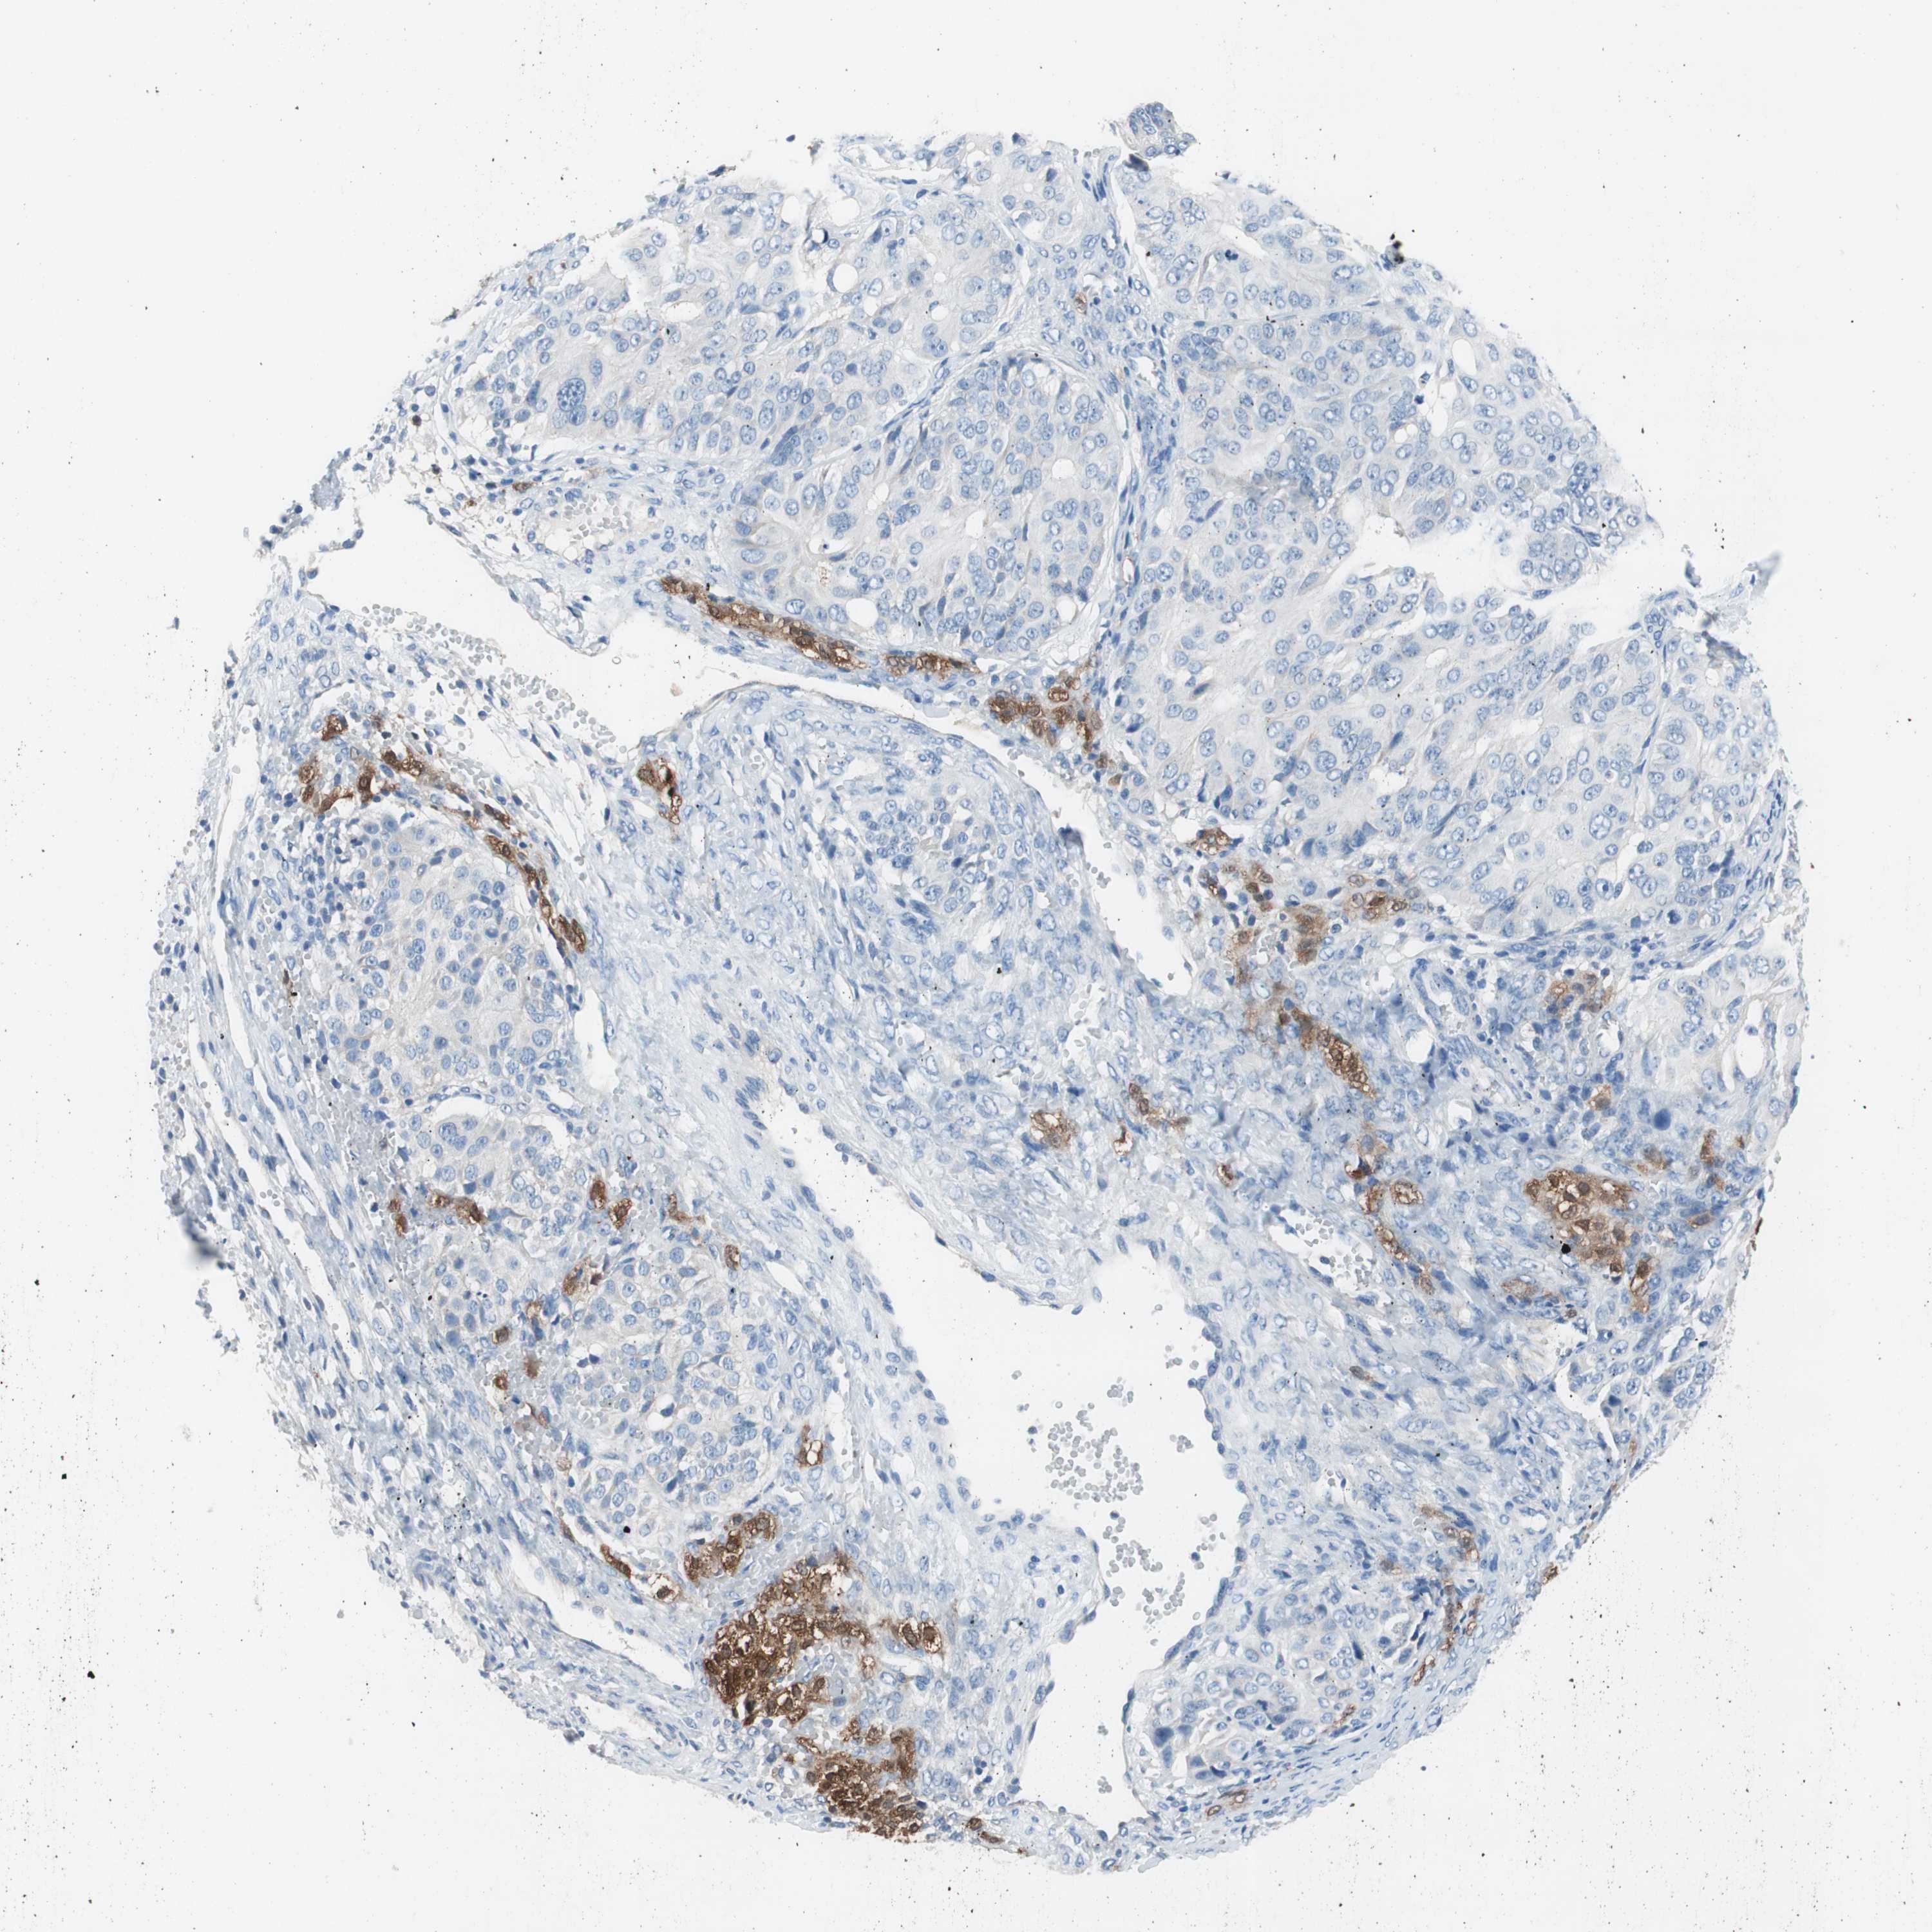

OVARIAN CANCER - Protein expressioni

A mouse-over function shows sample information and annotation data. Click on an image to view it in a full screen mode. Samples can be filtered based on level of antibody staining by selecting one or several of the following categories: high, medium, low and not detected. The assay and annotation is described here.

Note that samples used for immunohistochemistry by the Human Protein Atlas do not correspond to samples in the TCGA dataset.

Antibody stainingi

Antibody staining in the annotated cell types in the current human tissue is reported as not detected, low, medium, or high, based on conventional immunohistochemistry profiling in selected tissues. This score is based on the combination of the staining intensity and fraction of stained cells.

Each image is clickable and will lead to virtual microscopy that enables deeper exploration of all samples and also displays staining intensity scores, fraction scores and subcellular localization as well as patient and tissue information for each sample.

Antibody HPA008055

Staining

High

Medium

Low

Not detected

Intensity

Strong

Moderate

Weak

Negative

Quantity

>75%

75%-25%

<25%

None

Location

Nuclear

Cytoplasmic/membranous

Cytoplasmic/membranous,nuclear

Cystadenocarcinoma, serous, NOS

Carcinoma, endometroid

Carcinoma, NOS

Cystadenocarcinoma, mucinous, NOS